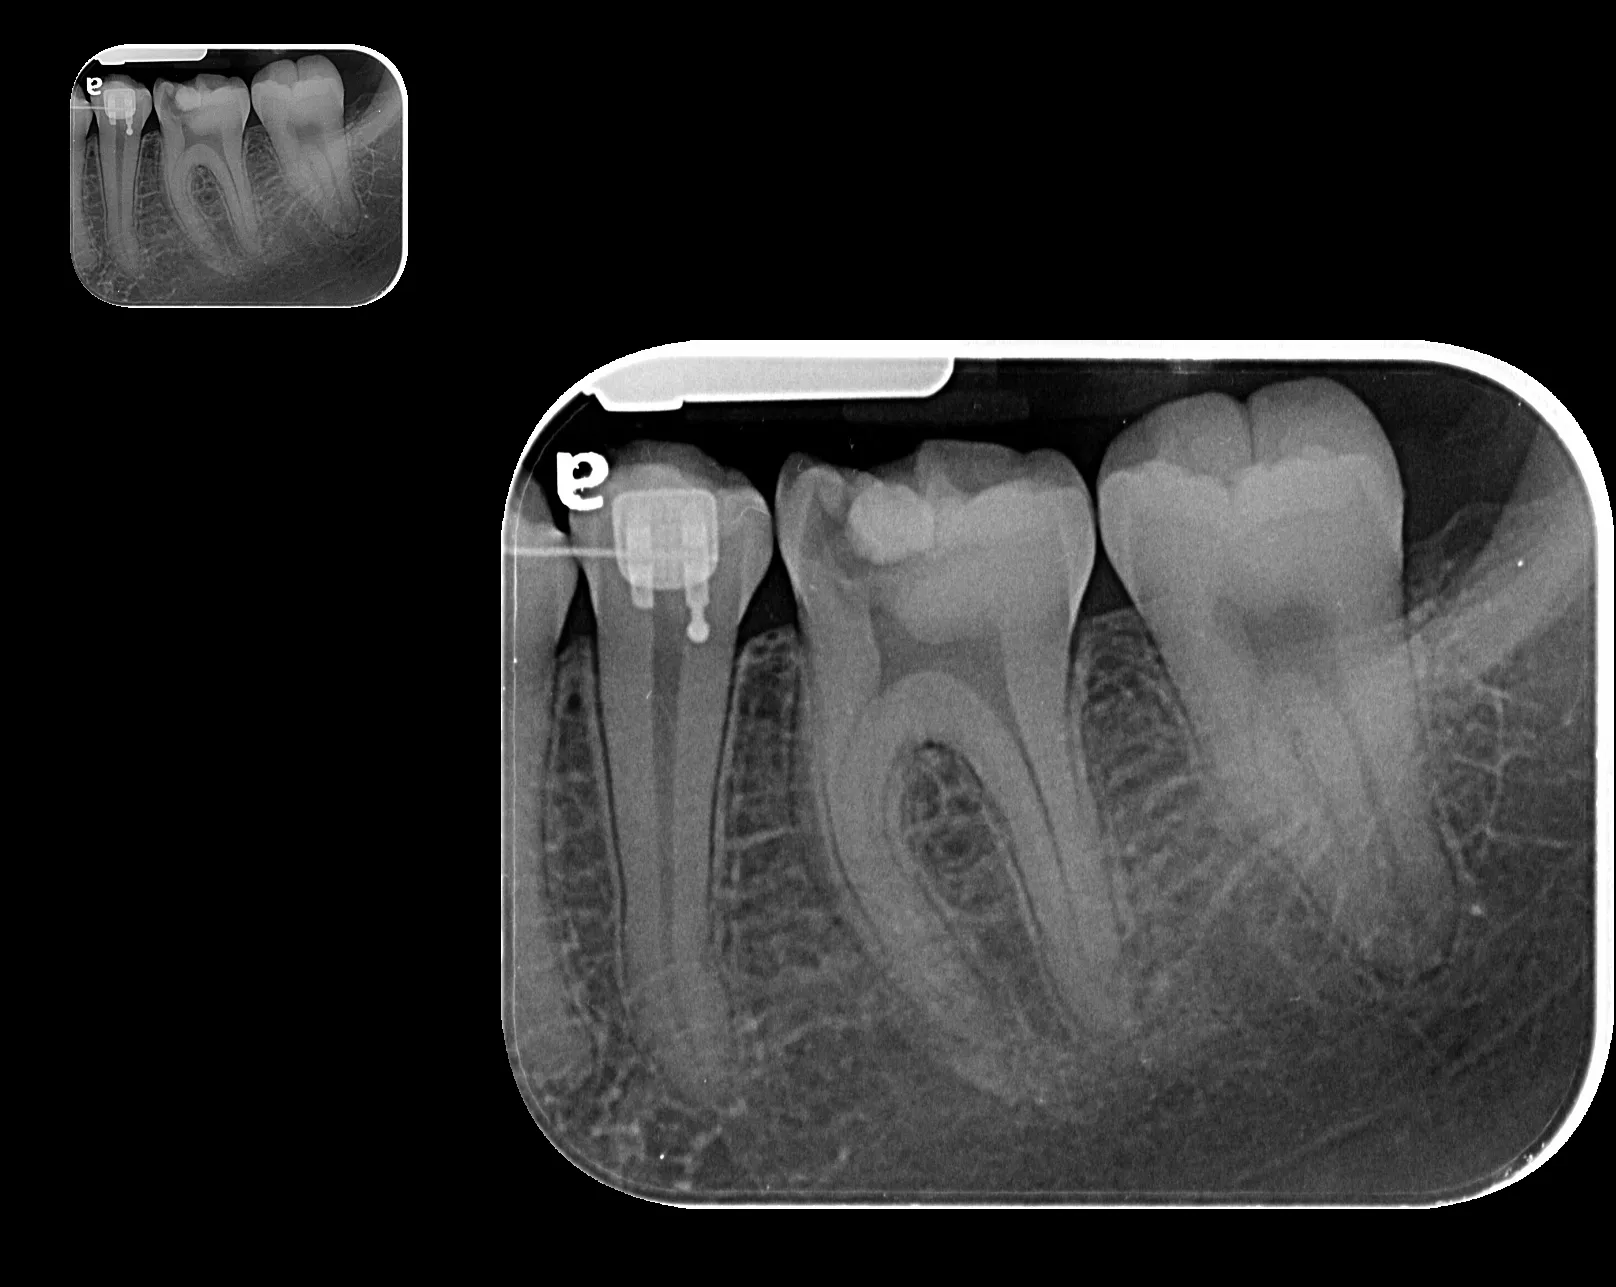

La radiografía intraoral permite observar con gran detalle los dientes y las estructuras que los rodean. Es una herramienta fundamental para detectar caries, infecciones, fracturas, alteraciones en la raíz dental o en el hueso de soporte.

• Ideal para tratamientos de endodoncia, implantología y control preventivo.